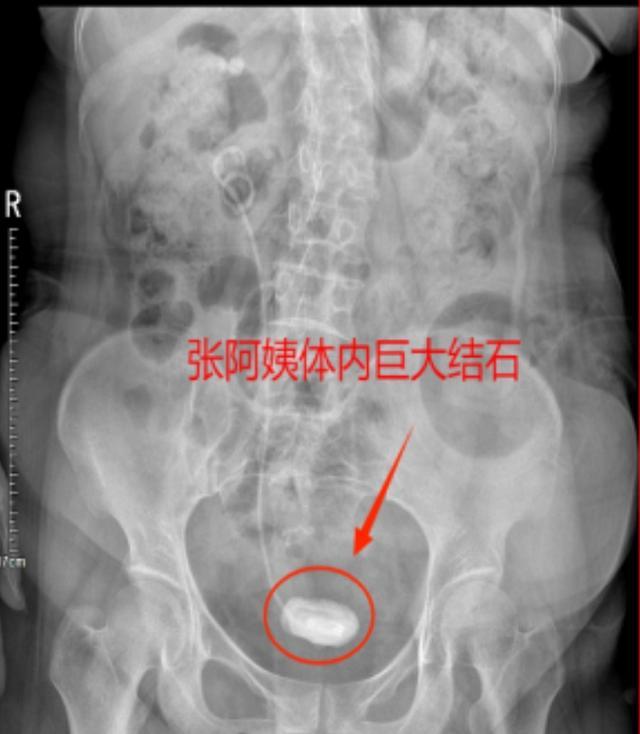

随着时间的推移,尿液中的沉渣在猪尾巴管两端弯曲处的管壁上逐渐沉积,最终形成了结石,导致张阿姨出现了反复尿痛的症状。

第一步,先处理张阿姨膀胱内的结石,通过钬激光碎石技术和输尿管软镜成功将结石击碎并取出,并更换了一根新的猪尾巴管,以确保尿液的顺畅引流。